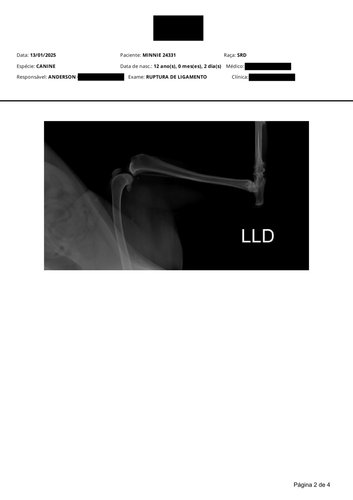

Gostaria de compartilhar com vocês uma situação delicada que estamos enfrentando. Minha cachorrinha Minne, que é uma parte muito especial da nossa família, rompeu o ligamento da coxa direita. Por causa da idade e do tamanho dela, a única forma de garantir que ela possa voltar a usar a patinha normalmente é através de uma cirurgia.